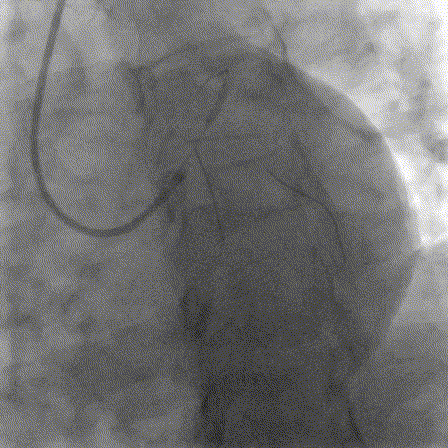

抽吸【例】量|【捷】谈血栓抽吸